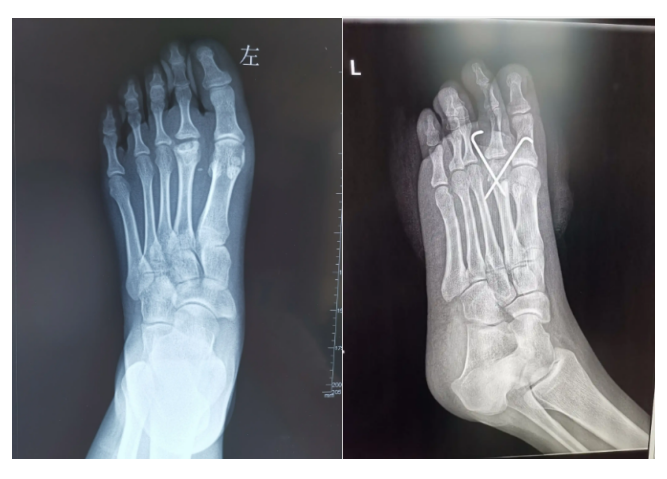

跖骨头背侧闭合楔形截骨术:由于近节趾骨的碰撞导致跖骨头背侧及上方的软骨面受累,跖侧关节面完好者。背侧作3-5cm的纵行切口,暴露跖骨头跖骨颈,关节内清创(避免过度清创,影响跖骨头血运),在背侧用摆锯于跖骨颈水平楔形截骨,跖骨头向近侧和背侧旋转,角度以将跖骨头正常跖侧部分带向背侧为度,尽量维持跖骨长度。交叉克氏针固定6周。并发症:转移性跖痛症;合并骨性关节炎的病例也取得良好疗效。在远端正常跖骨背侧行闭合楔形截骨,将跖骨头正常的跖侧部分翻向背侧,与趾骨关节面相对应。楔形截骨角度尽量维持跖骨长度,除了旋转外不要去除病变。,如果,跖骨头关节面彻底破坏,跖侧无足够的可用来重建关节面的软骨,已经形成终末期关节炎的患者,关节成形术或关节置换术,也是比较好的选择。多中心研究证明,即便4期的病变,术中探及背侧广泛关节面塌陷,但探查发现跖侧仍有足够关节软骨可供翻转上来重建关节面

我们的病例跖骨头背侧闭合楔形截骨术